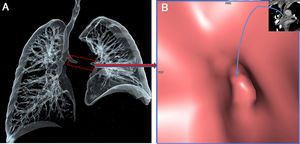

A 60-year-old male presented with complaints of chronic cough, occasional mucus secretion, and dyspnea. Coronal CT scans revealed diffuse thickened tracheobronchial wall (Fig. 1A). Axial CT scan showed atelectasi in the lingular segment of the left upper lobe (Fig. 1B). Three-dimensional volume-rendered air-specific coronal plan MDCT image (Fig. 2A) and virtual CT bronchoscopy (Fig. 2B) demonstrated obstruction of the left main bronchus. Bronchoscopic biopsy diagnosed diffuse tracheobronchial amyloidosis.

Fig. 1.

(A) Post-contrast coronal CT scan reveals diffuse thickened tracheobronchial wall. (B) Axial CT scan shows atelectasi in the lingular segment of the left upper lobe.